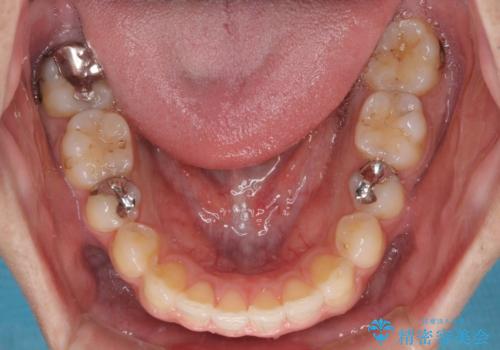

再矯正後の後戻りを防ぐため、歯列排列後に、下顎前歯はワイヤーによる固定を行いました。

下顎前歯の歯列を動かないようにしておくことで、上顎前歯の後戻り防止にも効果を発揮します。